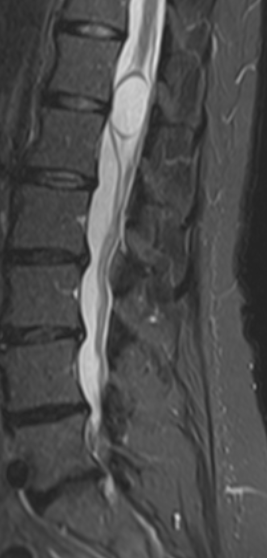

Les investigations menées par la suite ont permis la découverte d'un kyste médullaire épendymaire (bulle remplie de liquide située dans la moelle épinière). Sur une période de 5 mois, quatre interventions chirurgicales ont été réalisées, incluant l’installation d’une valve destinée à contrôler l’écoulement du liquide céphalo-rachidien (liquide protégeant le cerveau et la moelle épinière). Cette dernière permit, il y a quelques mois, de réduire considérablement la taille d'un kyste sans avoir recours à une chirurgie.